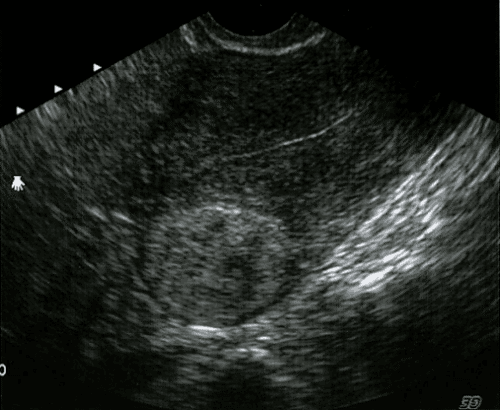

U XƠ CƠ TỬ CUNG: CÁC YẾU TỐ NGUY CƠ, HƯỚNG DẪN CHẨN ĐOÁN VÀ XỬ TRÍ